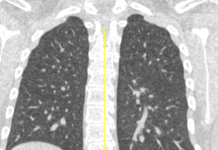

Al settimo giorno di terapia il paziente mostrava un modesto, ma progressivo, miglioramento del quadro clinico e laboratoristico, con discreta diminuzione dei valori di PCR, LDH; stabile la leucopenia. In decima giornata viene ripetuta l’indagine HRCT, per rivalutare il quadro radiologico, che ha documentato, in entrambi i polmoni, una riduzione sia degli addensamenti parenchimali con aspetto “a vetro smerigliato”, che delle aree con pattern “crazy-paving”, che tuttavia erano comunque ancora presenti nei campi medi ed in sede periferica, bilateralmente. Persisteva ancora l’ispessimento/stiramento della pleura viscerale in sede basale posteriore destra, dalla quale si dipartivano setti e tralci ad aspetto fibrosclerotico. Non era più visibile il versamento pleurico.

Durante la terza settimana di cura i tamponi per la verifica dell’infezione da Covid-19 si erano negativizzati. Così, dopo aver effettuato un’altra indagine HRCT, che ha documentato la pressocchè quasi completa risoluzione TDM degli addensamenti e dei reperti patologici parenchimali polmonari bilaterali già descritti, il paziente è stato dimesso.